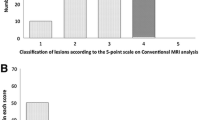

Circularity was lower in the irregular group (median 0.823, range 0.641–0.915) than in the round group (median 0.892, range 0.784–0.932, P = 3.21 × 10−10). Solidity was lower in the rough group (median 0.957, range 0.894–0.986) than in the smooth group (median 0.968, range 0.933–0.988, P = 1.53 × 10−4) (Fig. 4).

Correlations between subjective judgment and image analysis were good for shape and surface of the hepatic nodules (Fig. 4). Circularity correlated with a round shape, and solidity correlated with a smooth surface. In contrast, no gray values other than standard deviation correlated with subjective judgment of echogenicity. This discrepancy can be explained by the fact that the reviewers judged echogenicity of the hepatic nodules based on differences between the nodule and hepatic parenchyma. On the other hand, the combination of subjective judgment and image analysis improved the diagnostic accuracy for malignancy in this study.